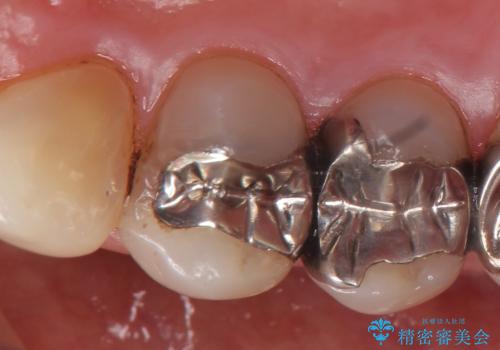

- 右上4番目の歯がなにもしなくてもズキズキ痛むといらっしゃった方の症例です。

検査の結果持続痛も認めたため、虫歯除去後根管治療を行いました。

虫歯治療は虫歯の進行度によって処置が変わってきます。

虫歯が小さければ、インレー・クラウン等による修復・補綴処置を行うだけで済みます。

しかし虫歯が大きくなると今回の症例のように神経処置や抜歯等をしなければならない場合もあります。